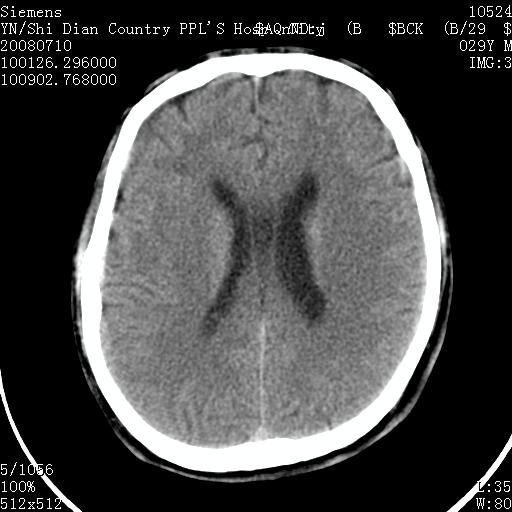

以下是引用随光逐影在2008-7-10 15:19:00的发言:[br]1)考虑左侧尾状核钙化。2)透间隔间腔与vergae腔并存。

以下是引用卜一在2008-7-10 16:43:00的发言:[br]1)考虑左侧尾状核钙化。2)透间隔间腔形成。支持!